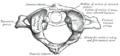

• الفقرة العنقية الأولى أو الفهقة Atlas: وهي أولى فقرات العمود الفقري وتكون حلقية الشكل، وتربط الجمجمة ببقية العمود الفقري. وليس لها جسم فقري لأن جسمها قد التحم مع الفقرة التي تليها (أثناء نمو الجنين). سطح الفهقة يكون بيضاوي الشكل أو على شكل كلية ويتمفصل نتوئين من الجمجمة. سطحها السفلي يكون مستديراً. اما شوكتها فهي صغيرة جداً وهي بشكل مرتفع صغير. لأنها لو كانت كبيرة لكانت قد أعاقت حركة الجمجمة خاصة إلى الخلف (أي عند النظر لأعلى)، بينما يكون النتوءان المستعرضان طويلان وهي تعمل كعتلة للعضلات التي تدير الرأس.